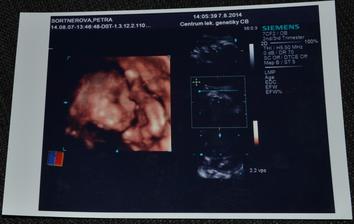

* 7.8.2014 - 4D ultrazvuk - jelikož je placenta na přední straně a Ellinka před sebou měla ještě pupeční šňůru a nohy, tak fotky nejsou nic moc... Ale nevadí. i tak je nádherná